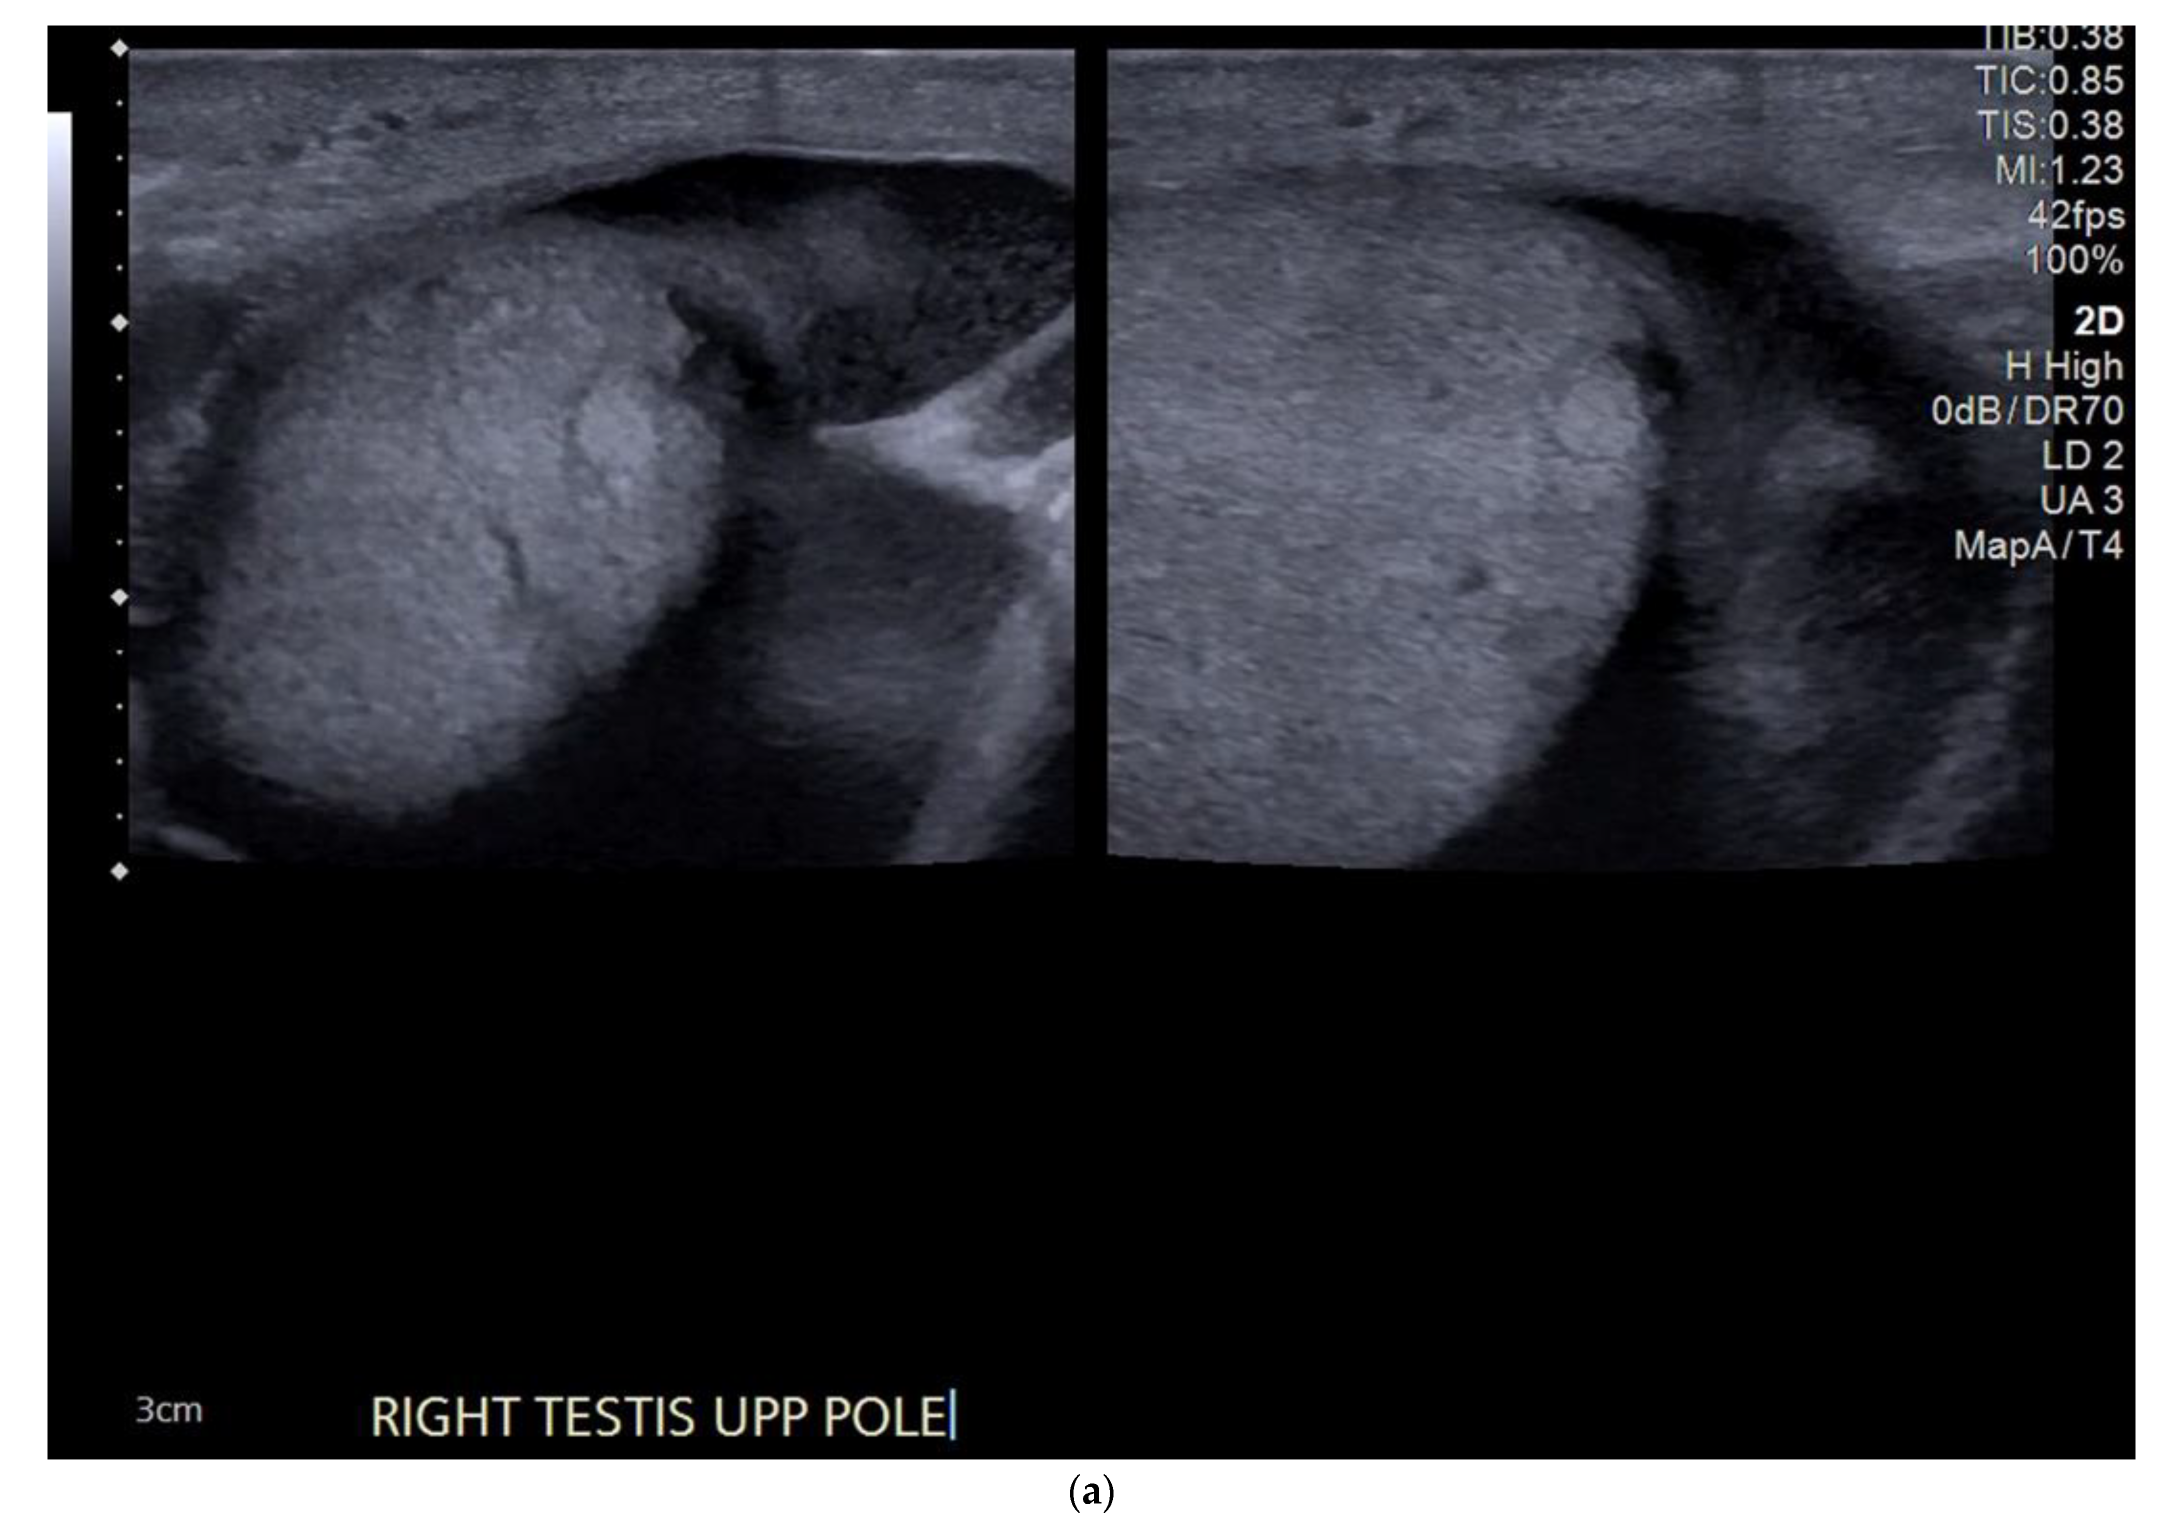

4.1. Seminomatous Germ Cell Tumour

| Seminomas | Homogenous and hypoechoic Well circumscribed Occasionally contain cystic components or calcifications |